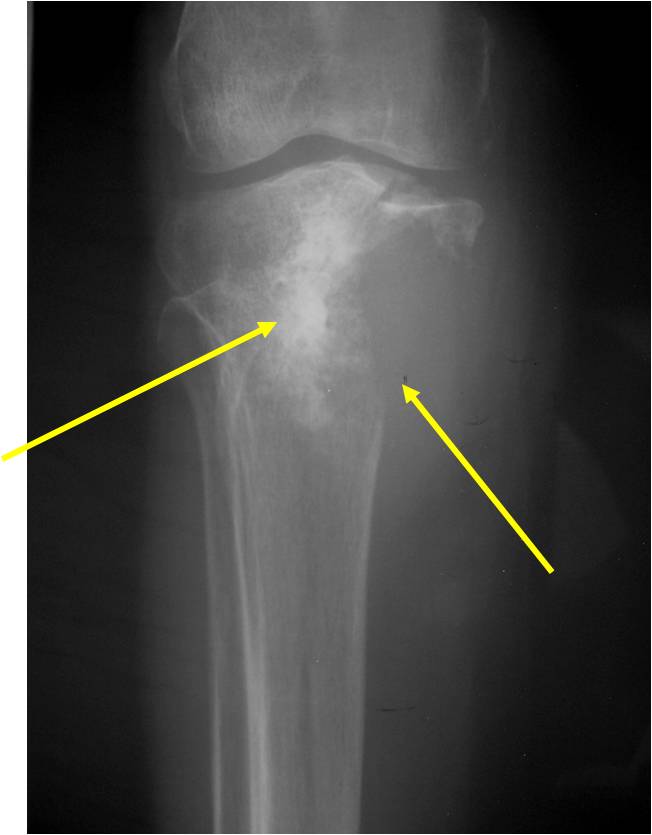

Radiology emulates pathology: Biphasic Tumor

- One region low grade chondrosarcoma

- Second more aggressive area with bone destruction, lysis of calcification, soft tissue mass

- Cortical permeation and a soft tissue mass in 70% of cases

Ill-defined, lytic intraosseous lesion

- Or extraosseous soft tissue mass

- Devoid of calcifications in continuity with lesions having the features of a cartilaginous tumor

Characteristically abrupt transition between chondroid tumor and dedifferentiated, lytic component

Bone may be expanded and adjacent cortex thickened

(Right Arrow)Aggressive Lytic Area (Dedifferentiated Sarcomatous Component) Cortical Destruction Soft Tissue Mass without Calcification